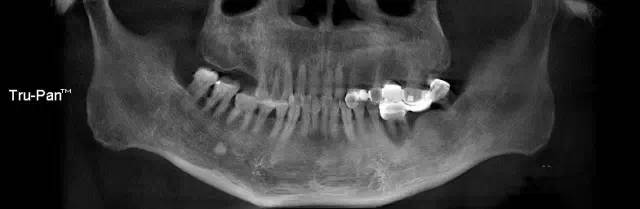

第四圖:上頜竇發(fā)育不足,上頜竇底骨高度充裕,通常頰側(cè)骨壁超級厚,看下圖2.臨床上種植常不需要提升措施。(如需提升,切記頰側(cè)骨厚度過大,開窗的困難性劇增)